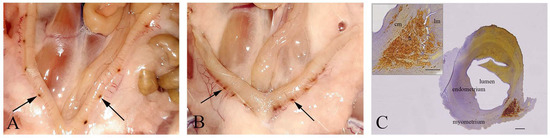

2.3. Histological and Stereological Analysis of the Placenta of 21-Day-Old Fetuses